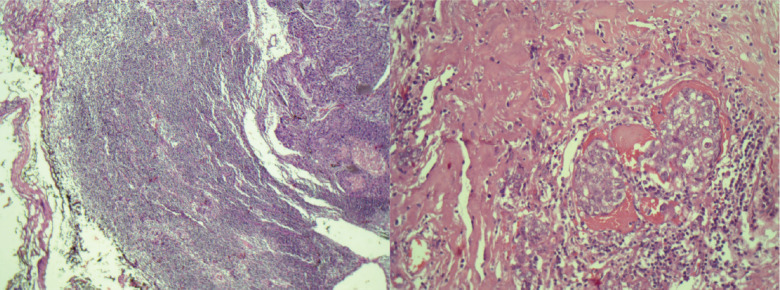

Background: Sebaceous carcinoma of the breast (SCB) is an unusual neoplasm. To the best of our knowledge, only 30 cases have been reported in the literature. Due to its rarity, there is limited knowledge on how to manage patients with SCB. This article aims to describe a case of multicentric sebaceous breast carcinoma in a 33-year-old woman detailing the diagnostic process, historical findings and the treatment approach.

Abstract Image